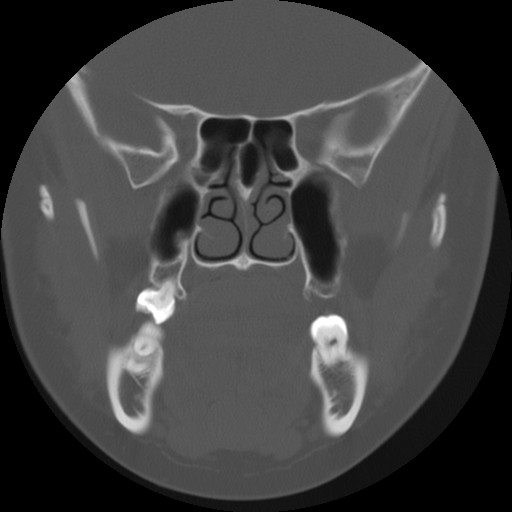

Identify the nasal turbinates, maxillary and ethmoid sinus. Click the image for labeling.